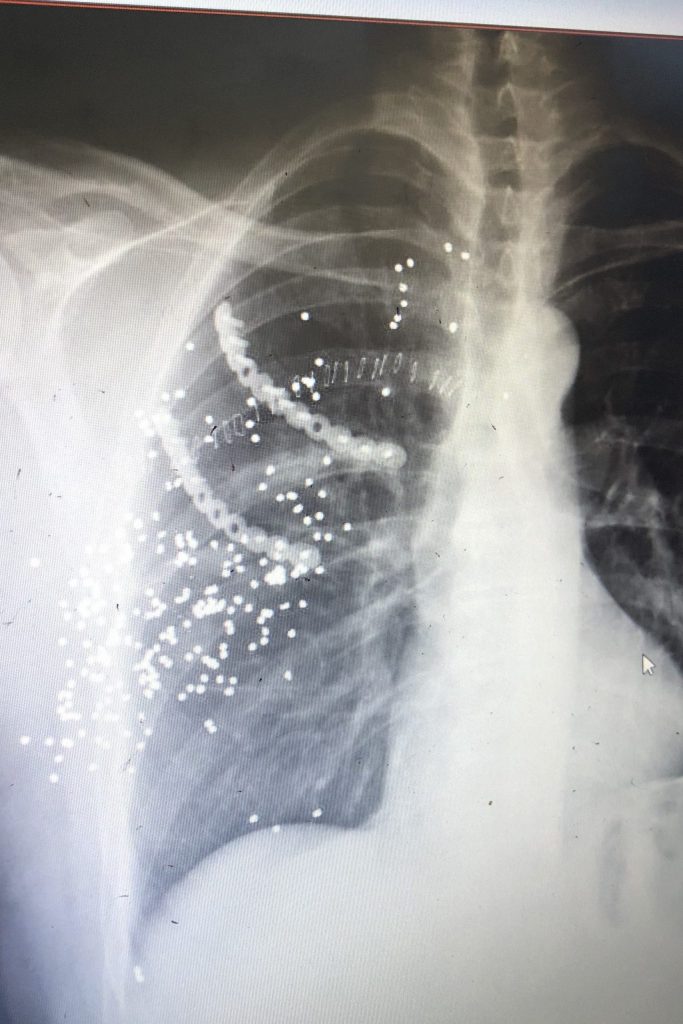

Beglaubigte Übersetzung des Arztberichtes Attentat…